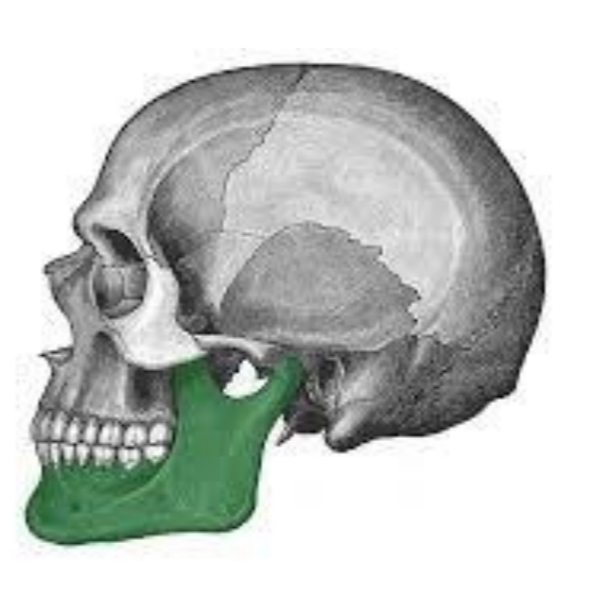

Gives shape to chin or jaw

Consists of one bone that is horseshoe shaped

Mandible